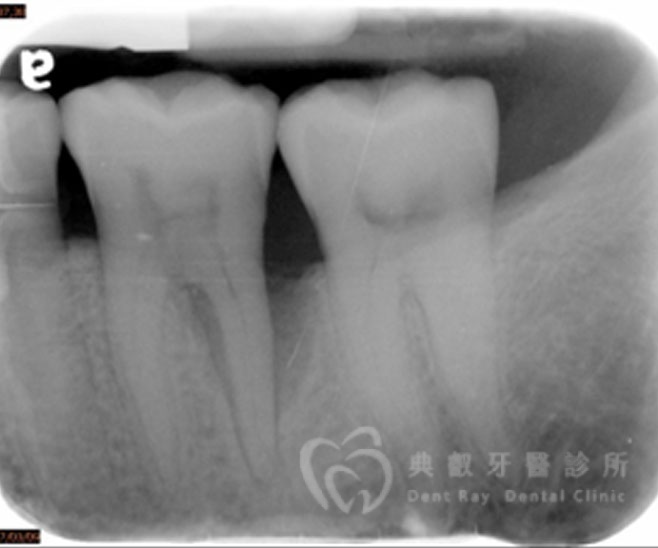

牙周手術案例二

術後兩個月